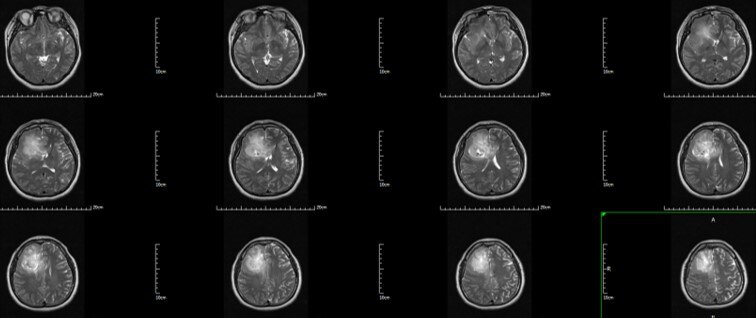

术前T2 Flair:右额-胼胝体-岛叶胶质瘤

术前T2